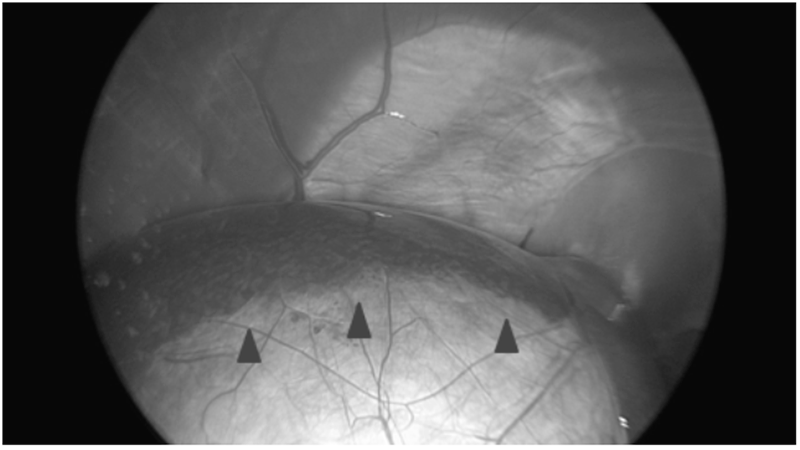

(팽창된 담낭이 일부 염증을 유발하여 주변 간엽 끝부분과 유착되어 들러붙어 있는 것이 확인됩니다. ▲ (화살표 머리)

사진에서 표현이 되진 않지만, 담낭이 많이 팽창되어 있어 수술기구로 담낭을 붙잡을 수 없는 상태였고, 그래서 담낭관을 우선 분리하는 기존 방식과 다르게 담낭을 간에서 먼저 분리하는 (Fundus-first) 방식으로 수술을 진행했습니다.)